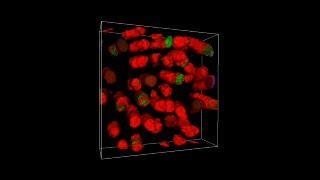

This video explains how mutant opsin aggregates in rod photoreceptor outer segments.

(Photo Credit: Haeri et al.)